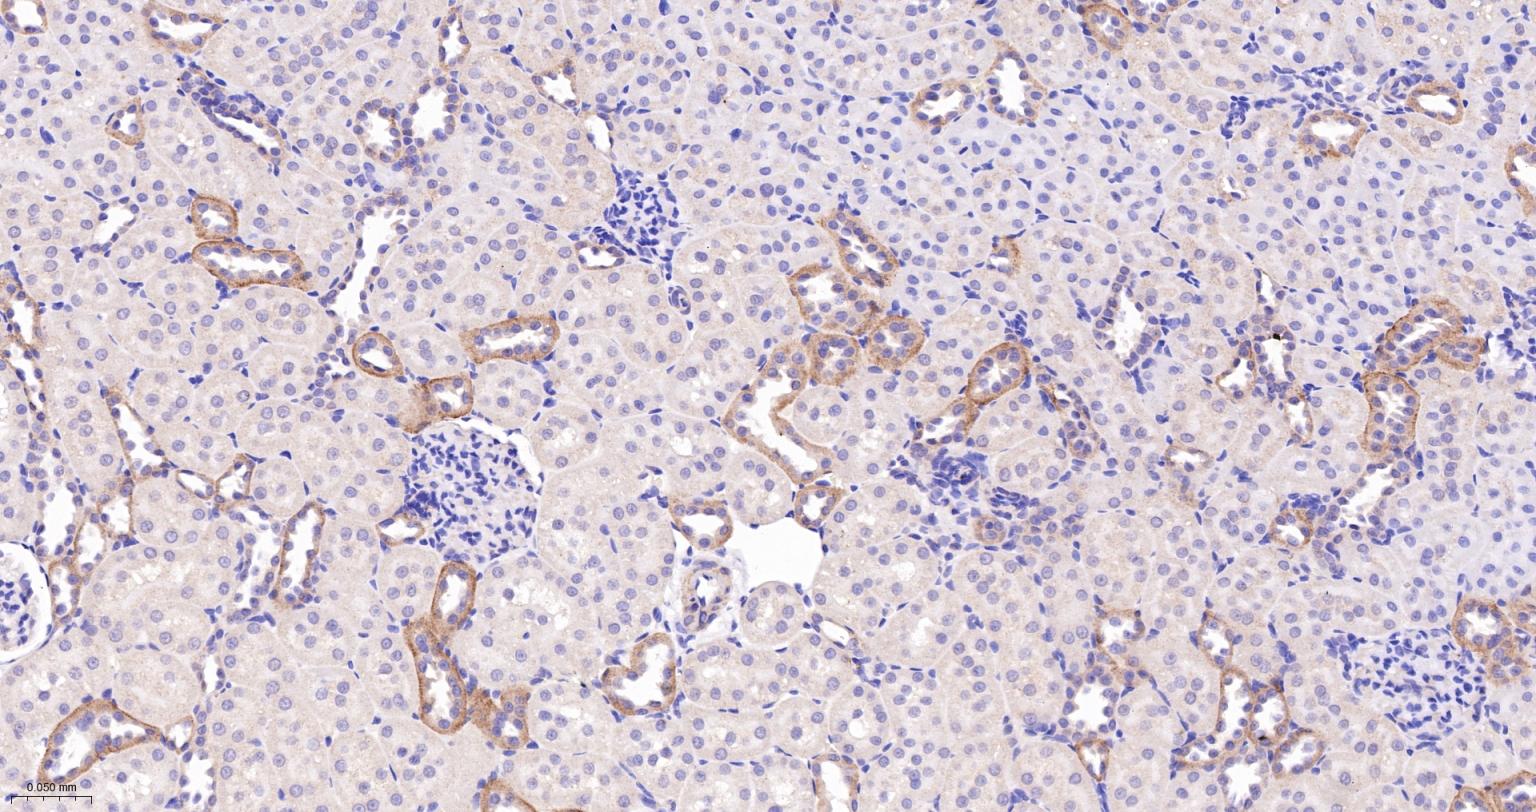

Paraformaldehyde-fixed, paraffin embedded Rat Kidney; Antigen retrieval by boiling in sodium citrate buffer (pH6.0) for 15 min; The section was incubated with NWASP Monoclonal Antibody, Unconjugated (bsm-61522R) at 1:200 overnight at 4°C, followed by conjugation to the bs-0295G-HRP and DAB (C-0010) staining.

Paraformaldehyde-fixed, paraffin embedded Mouse Kidney; Antigen retrieval by boiling in sodium citrate buffer (pH6.0) for 15 min; The section was incubated with NWASP Monoclonal Antibody, Unconjugated (bsm-61522R) at 1:200 overnight at 4°C, followed by conjugation to the bs-0295G-HRP and DAB (C-0010) staining.